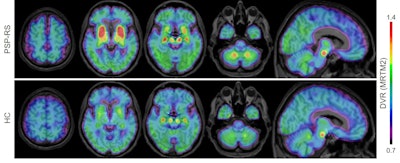

Brendel and colleagues evaluated nine male and eight female patients (mean age, 70 ± 7 years) with suspected cases of progressive supranuclear palsy. The 17 patients underwent F-18 PI-2620 PET scans at four different imaging centers, along with 10 healthy controls and seven disease controls who had been diagnosed with multisystem atrophy, Parkinson's disease, or Alzheimer's disease.

PET images were acquired within 60 minutes after injection of F-18 PI-2620 and then coregistered to an MRI template. The researchers also calculated standardized uptake value ratios (SUVr) of key brain regions in the basal ganglia and dentate nucleus, including the globus pallidus, substantia nigra, and subthalamic nucleus. They used the cerebellum as the reference region.

He and his colleagues also observed significantly greater mean SUVr of F-18 PI-2620 in PSP patients' globus pallidus (1.34 ± 0.16; p = 0.001) and the substantia nigra (1.33 ± 0.14; p = 0.003) compared with healthy controls (1.12 ± 0.09 and 1.15 ± 0.08, respectively).

They found no statistically significant difference in mean SUVr in the globus pallidus (1.11 ± 0.06) and only a slight elevation in the substantia nigra (1.23 ± 0.09) among the disease control subjects compared with the healthy controls. The commonality in these two groups would suggest that F-18 PI-2620 was able to distinguish between patients with PSP and individuals with another form of neurodegeneration.